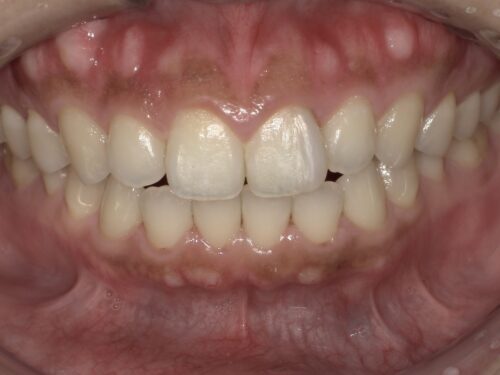

あとは、この前歯の端っこの古くなったコンポジットレジンを、

削りとって、

新しい白いコンポジットレジンで詰め直します。

どうでしょうか。

それぞれの段階で見比べてみましょう。

治療前

ホワイトニング後

コンポジットレジン後

詰め物を新しくした後は全体が白くなって、かつ、前歯のところも違和感がないですよね。